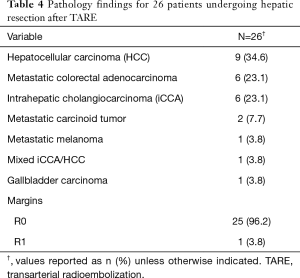

Pathology of the underlying disease is given in Table 4. The majority of patients had primary hepatic malignancy (n=16, 62%). Of available (n=17) histologic descriptions of tumor necrosis, 76% (n=13) demonstrated extensive or complete pathologic necrosis.